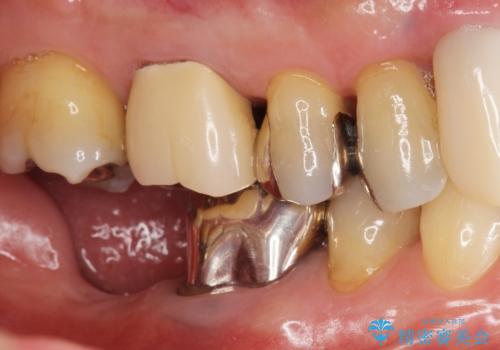

[ 重度歯周病 ] インプラント・義歯による咬合再構築

![[ 重度歯周病 ] インプラント・義歯による咬合再構築の症例 治療前](https://seimitsushinbi.jp/wp/wp-content/uploads/2021/07/0a652e75d5f31b51f66fbb3c46093249-500x350.jpg?v=1626759388)